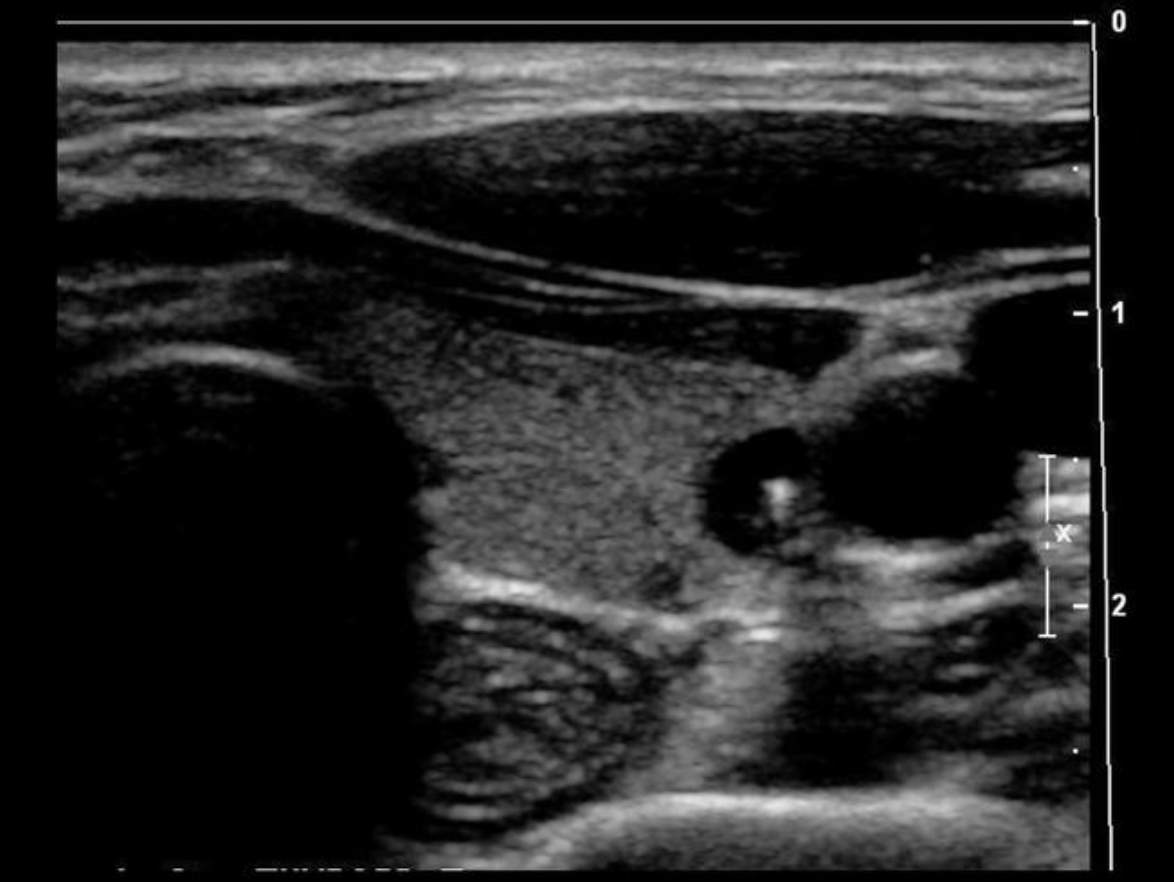

Which blood vessel is located lateral to the left lobe of the thyroid and demonstrates an anechoic ovoid shape in a transverse view of the mid thyroid?

B. left internal jugular vein

The internal jugular vein is located lateral to the left lobe of the thyroid and demonstrates an anechoic ovoid shape in a transverse view of the mid thyroid. The carotid artery is also lateral to the thyroid lobes but it should be a circular structure.

The image displays the left lobe of the thyroid with the circular CCA immediately lateral to the mid lobe and ovoid IJV lateral to the CCA.

Which blood vessel is located lateral to the right lobe of the thyroid and demonstrates an anechoic circular shape in a transverse view of the mid thyroid?

C. right common carotid artery

The right common carotid artery is located lateral to the right lobe of the thyroid and demonstrates an anechoic circular shape in a transverse view of the mid thyroid.

Find the internal jugular vein

The common carotid artery is lateral to the thyroid gland. The internal jugular vein is slightly anterior and lateral to the common carotid artery.